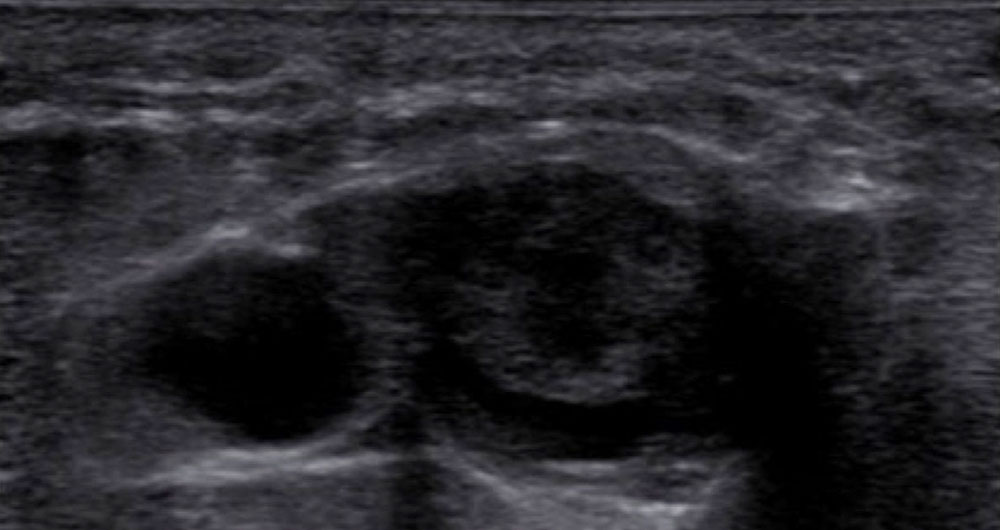

The most important imaging to detect or exclude phlebothrombosis is sonography. The affected vein section shows the thrombus contained in the vessel lumen, which cannot be compressed by compressing the vein with the transducer. Depending on age, this vascular thrombus tends to have a relatively low echogenicity initially in acute cases. The vein diameter is significantly increased by the intraluminal thrombus in the acute phase. In color-coded duplex sonography (CCDS), no color signal is found in the vein owing to the lack of blood flow, even at very low PRF settings (low pulse repetition frequency PRF = high detection sensitivity for flowing blood). With increasing thrombus age, the thrombus shrinks in size and becomes increasingly echogenic. In the further course, at least partial recanalization of the thrombosed vein occurs in favorable cases. Often beginning at the vein wall, blood (echo-free on ultrasound) again flows through the vessel surrounding the thrombus.